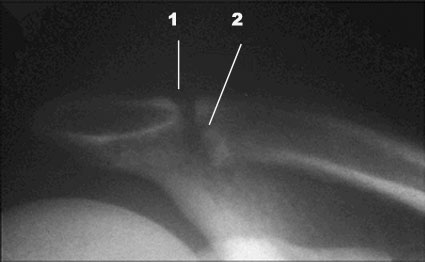

X-rays often appear normal in the early clinical course.

With time, loss of subchondral bone detail in the distal clavicle, microcystic changes in the subchondral area (2), and widening of the AC joint (1) may be seen.